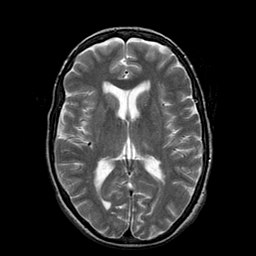

Metastatic Adenocarcinoma of the Colon: T2-weighted MR -- Slice #13

[Home][Help][Clinical] Slice 13